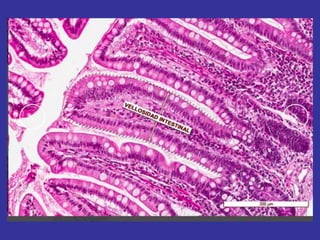

A-Celulas plasmáticas inflamación crónica

C- Intestino delgado eosinofilos

células plasmáticas Derivadas delos LINFOCITOS B En los tejidos conjuntivos su vida media es de 10 a 20 días. Su función es sintetizar y secretar los anticuerpos (proteínas ) inmunoglobulinas. Ig Su número aumenta en los tejidos con procesos inflamatorios crónicos (parasitismo). Abundan en la mucosa digestiva, incrementándose durante la digestión, en los órganos genitales durante el embarazo

A-Celulas plasmáticas inflamacióncrónica B- Inflamación aguda neutrófilos C- Intestino delgado eosinofilos